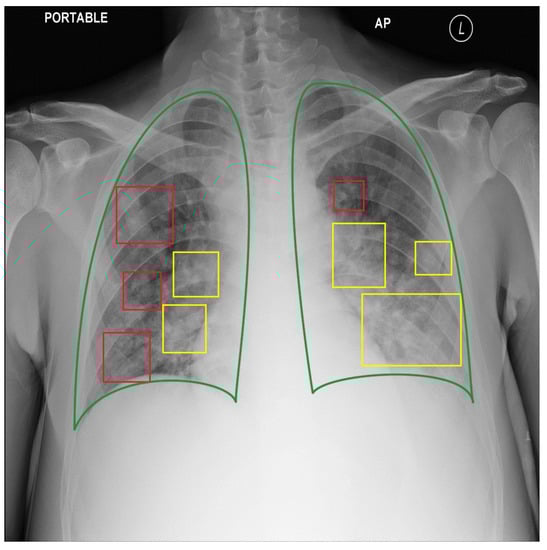

- We standardized three public datasets into the COCO format standard for a 2895 CXRs dataset with 7943 bounding box annotations for three types of COVID-19 lung lesions. We also reannotated the three public datasets to evaluate our model. Finally, we provide our 235 lung-lesion annotated COVID-19 CXRs with 1192 annotations collected since the first outbreak in a province of northern Vietnam. All evaluation data were annotated by our experienced physicians. These data significantly encourage reproducibility.